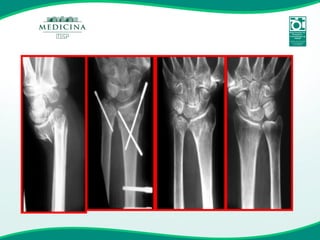

Fixador externo e fios de Kirschner

Fratura instável & Osteoporose

Fratura Instável

Fixação Interna